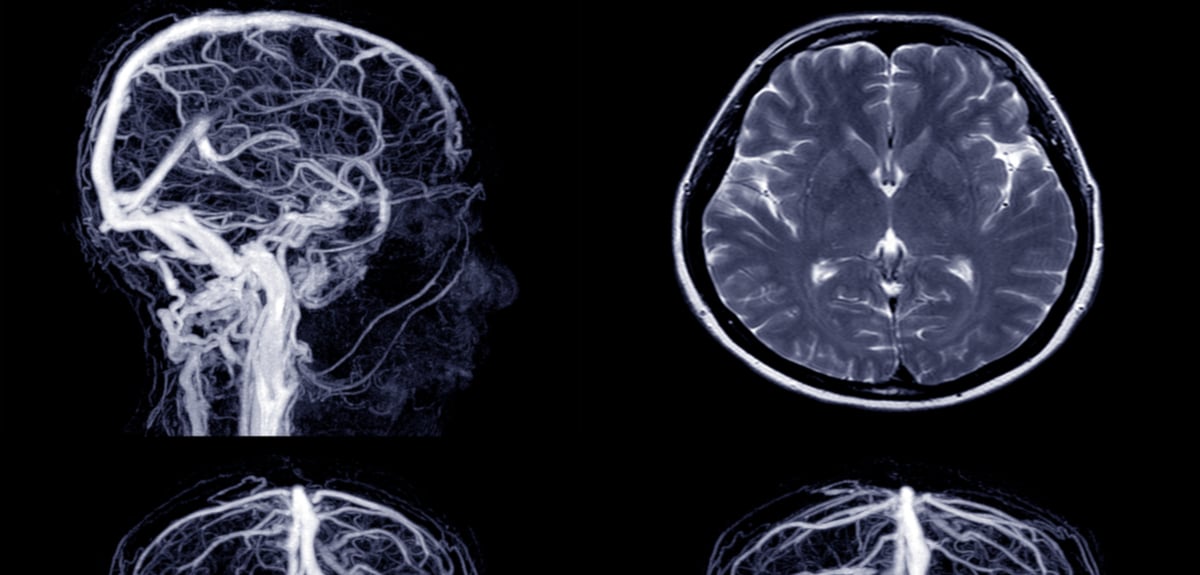

This can happen if an artery that feeds blood to the brain gets clogged, or if it tears and leaks. Definition of stroke (entry 2 of 3). A stroke is when there is a lack of blood flow to the brain. A varient can play instead of a stroke loop based on the % chance set by the varient slider. What is a mouse gesture? Explanation for the 'stroke it' phrase in the phrases.com dictionary. It may not totally reverse the effects of your stroke, but it can help you regain your independence and recover some of what was. There are two types of strokes. I like to stroke it before bed. Strokeit is an advanced mouse gesture recognition engine and command processor. A stroke is an illness in which part of the brain loses its blood supply. #gmm 1152 #musings #poke it #stroke it #love it like we know you do #rhink. Stroke is a disease that affects the arteries leading to and within the brain.

A stroke is an illness in which part of the brain loses its blood supply. Stroke it is proud and honored in congratulating will brito on graduating from northwestern university. A stroke is when there is a lack of blood flow to the brain. The game plays mainly stroke loops chosen at random (the game will try to avoid loop repetition where it can). One is when there is a blood clot blocking the artery. Definition of stroke (entry 2 of 3). 5 cause of a stroke occurs when a blood vessel that carries oxygen and nutrients to the brain is either blocked by. What does stroke it expression mean? A blow with a weapon or implement. A stroke rehabilitation program can help your brain get the job done. There are two types of strokes. Definition of stroke it in the idioms dictionary. (intransitive, colloquial, vulgar) to masturbate.

Explanation for the 'stroke it' phrase in the phrases.com dictionary. A stroke is an illness in which part of the brain loses its blood supply. In his first season with the stroke it cast, the team's most senior member provided the veteran. Strokeit plugins go open source. Sean likes to stroke it in bed in front of a piture of his dad. In short, it's a nifty little program that lets you control your computer by drawing shapes with your mouse. A varient can play instead of a stroke loop based on the % chance set by the varient slider. Obiettivi del progetto prevenir / stroke. What is a mouse gesture? A stroke occurs when the blood supply to part of your brain is interrupted or reduced, preventing brain tissue from getting oxygen and a stroke is a medical emergency, and prompt treatment is crucial. Strokeit is an advanced mouse gesture recognition engine and command processor. There are two types of strokes. One is when there is a blood clot blocking the artery.